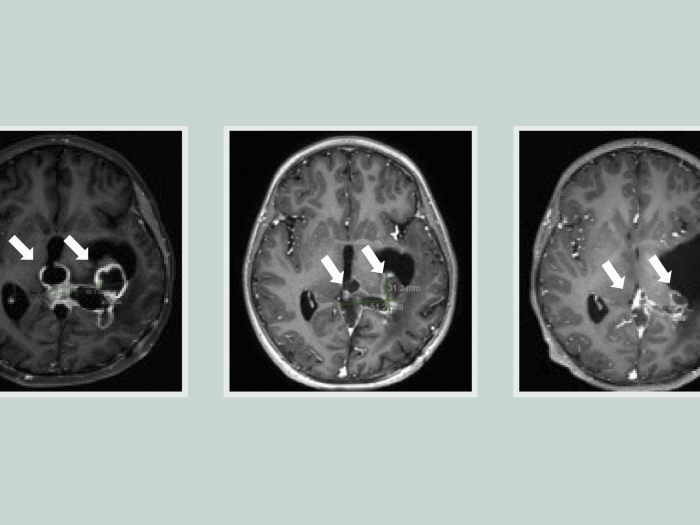

Michigan Medicine neurosurgeon B. Gregory Thompson, M.D., performed surgery to "clip" the aneurysm. During surgical clipping, small metal clips are placed around the base of the aneurysm, essentially depriving an aneurysm of its blood supply and preventing rupture.

"Dr. Thompson left 13 pieces of hardware in my head, including three clips," Poole says.